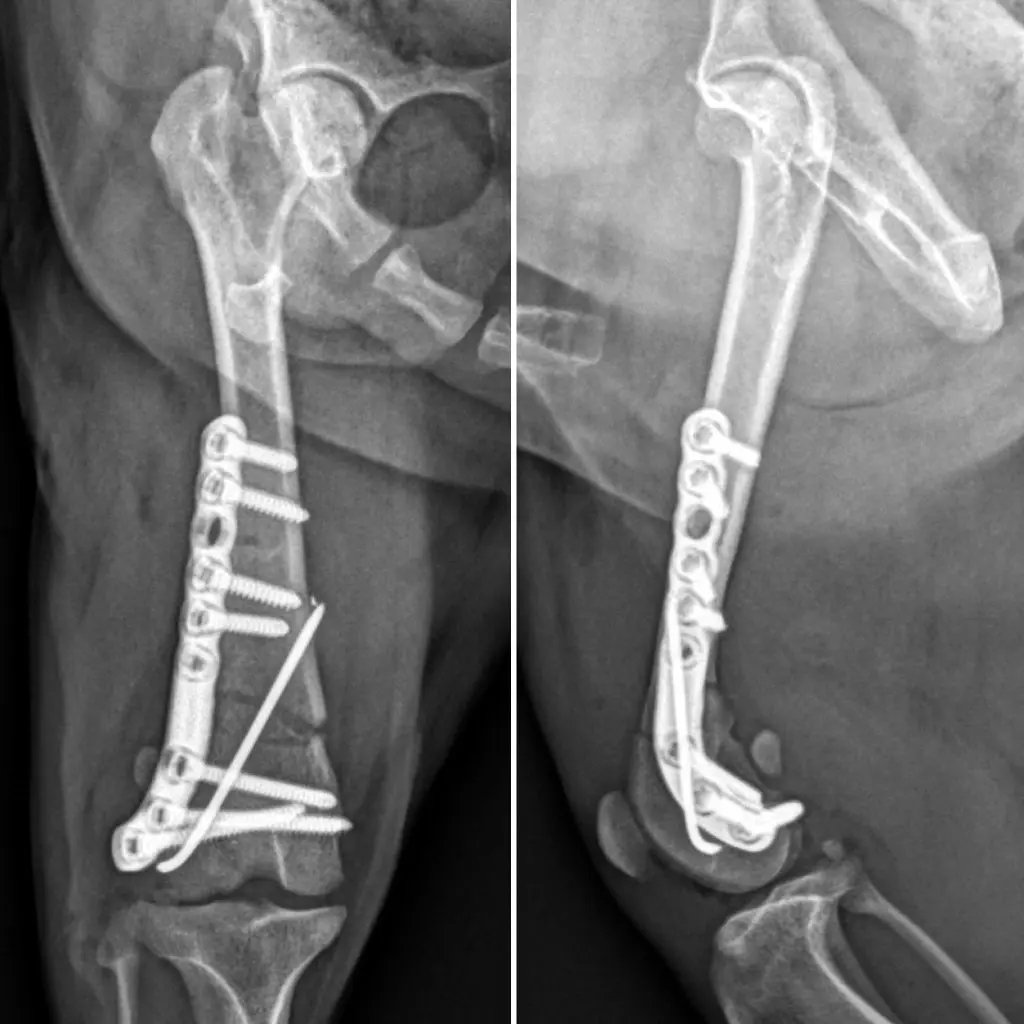

Cerramos la herida quirúrgica por planos siguiendo la técnica convencional, y finalizamos con un nuevo estudio radiológico que confirmó la correcta alineación ósea y la adecuada colocación de los implantes.

Actualmente, Pitu se encuentra en recuperación, con controles veterinarios periódicos y fisioterapia adaptada a su edad y condición. Su evolución está siendo muy positiva, y su espíritu alegre sigue intacto.